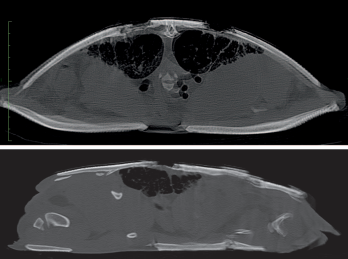

Sagittal and transverse computed tomography (CT) images of penetrating lesions and bone lysis in an Aubry’s

flapshell turtle (Cycloderma aubryi) 11 weeks after initial presentation.